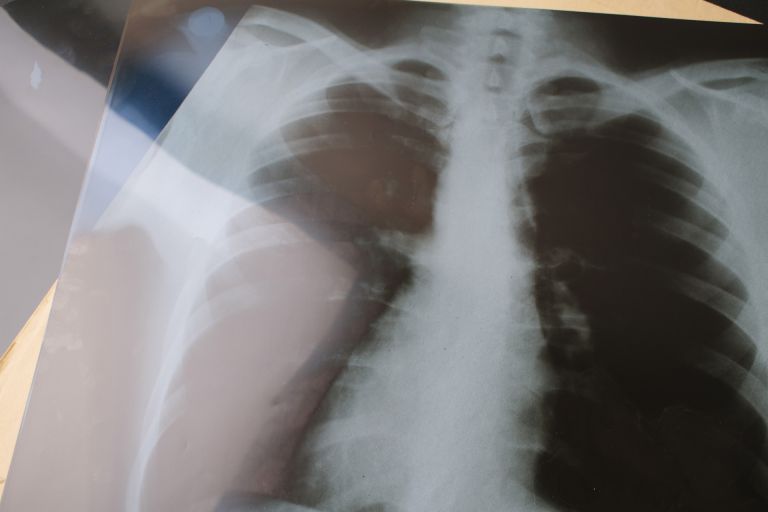

これらの医療機関では総合的な内科診療のほか、発熱外来や健康診断、各種予防接種への対応もあり、多忙な都市生活者の健康維持を支えている。この地域には歴史ある病院も存在し、地域医療の核として役割を果たしている。救急医療にも強い体制を持つ総合病院も複数存在し、発作や急な体調変化が生じた場合にも24時間体制で受け入れを行っている。特に内科に関しては、専門外来や高度な治療機器を備えているため、慢性的な疾患だけでなく緊急性の高い症例にも速やかに対応できる。高齢化が進む都市部において、こうした医療機関による細やかなフォロー体制や在宅療養への支援も、患者からの信頼を得ている理由の一つとなっている。

特に医療の充実はこの地域の大きな特徴で、交通利便性の高さから周辺自治体からも多くの患者が訪れます。内科を中心とした診療所や病院はさまざまな場所に点在し、夜間や休日対応、ネット予約の活用など、多忙な都市生活者への利便性向上が図られています。歴史ある総合病院も地域医療の中核を担い、24時間体制の救急対応や高度な内科治療が行われています。また、多職種連携により高齢者や慢性疾患患者への包括的なサポート体制も整備され、住民だけでなく観光客や短期滞在者にも安心感を提供しています。地域医療現場では患者本位のサービス向上が進み、きめ細やかな対応が評価されています。